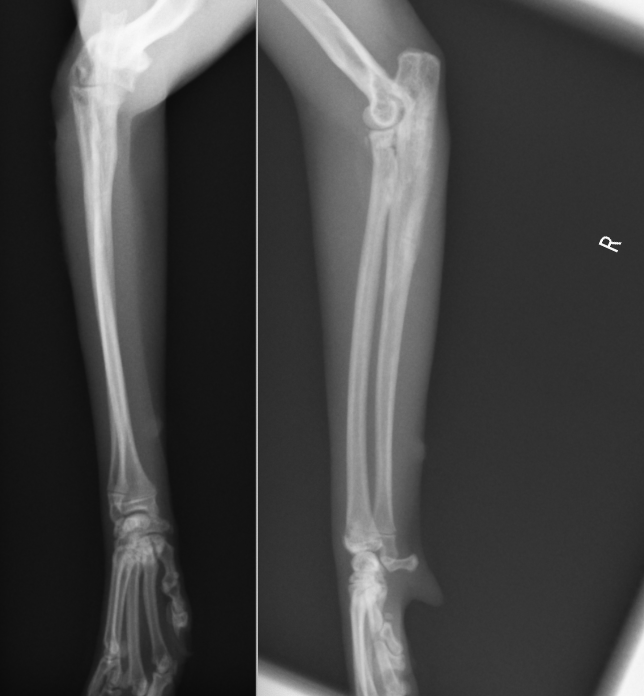

今回の症例はキャットタワーから落下して足を上げてしまうとのことで来院しました。尺骨の近位が骨折し、橈骨が外側に変位してしまっています。診断はモンテジア骨折Ⅲ型でした。全く足をつくことができないため、手術が必要と判断し行いました。

正面から撮影したX線の拡大です。紫が尺骨の骨折で、緑が、脱臼した橈骨になります。

横から撮影したX線の拡大です。左が正常の骨で、右が骨折した骨です。